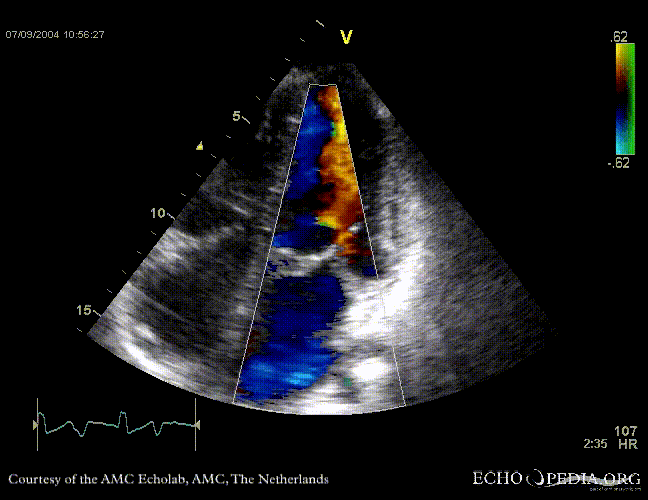

Case 11

| Courtesy of: J. Vleugels, AMC, The Netherlands | |

| Sarcoidose 2 | Sarcoidose 5 |

| Sarcoidose 7 | Sarcoidose 8 |